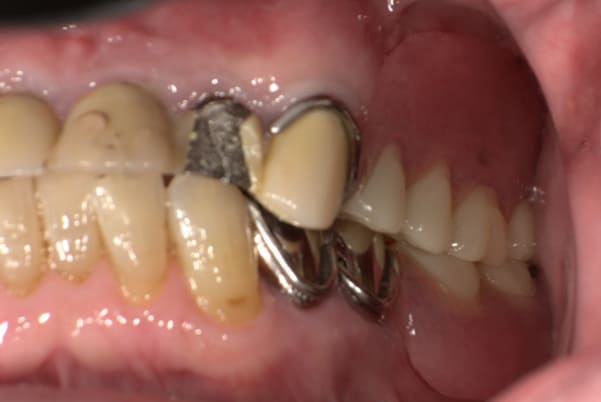

入れ歯が沈み込むことを防止するストッパーがない入れ歯を装着されていたため、お食事により入れ歯が沈み込みお痛みがでている状態でした。

笑った際に、太いバネが左右に見えるため、あまり大きく笑うことを避けていらっしゃいました。

作製した入れ歯は、お食事の際に入れ歯の沈み込みを予防するため、適切なストッパーを付与することで、入れ歯は沈み込まなくなり、お痛みは消失しました。

右下のバネの位置は後ろに、左下のバネは見えづらい形態のバネを用いる設計とすることで笑った際にバネが見えないようになり、気にされることはなくなられました。

裏側の見えない部分は金属を用いることで、お食事の際の入れ歯の動き、沈み込みを抑えお痛みがでづらく、入れ歯の動きが抑制されることで、長期的に残りの歯に負担のかかりにくい設計としました。